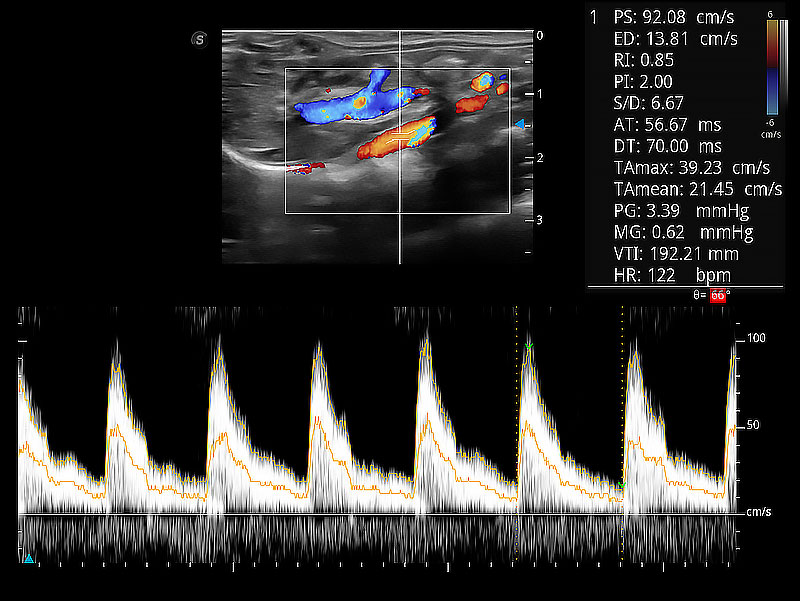

隨著取樣門位置改變,頻譜多普勒包絡(luò)可進(jìn)行自動(dòng)眼蹤測(cè)量,且可自由配置測(cè)量的參數(shù)。